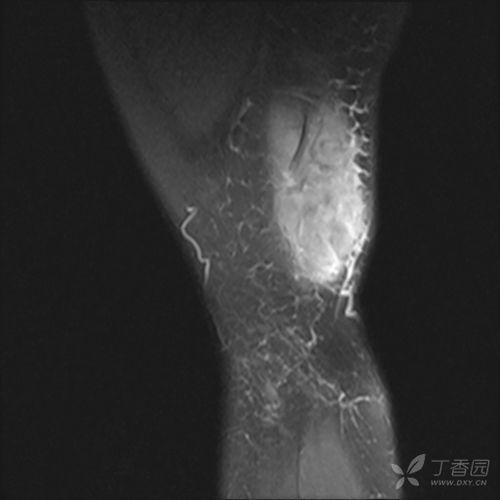

首先,得先弄清楚什么是股外侧肌注射。简单来说,这是一种常见的医疗操作,通常用于给成人注射药物。股外侧肌位于大腿外侧,是注射的理想部位,因为这里肌肉丰富,血管较少,注射时相对安全。

1. 选择注射部位:在大腿外侧找到股外侧肌,通常在髌骨下缘与髂前上棘连线的中点附近。